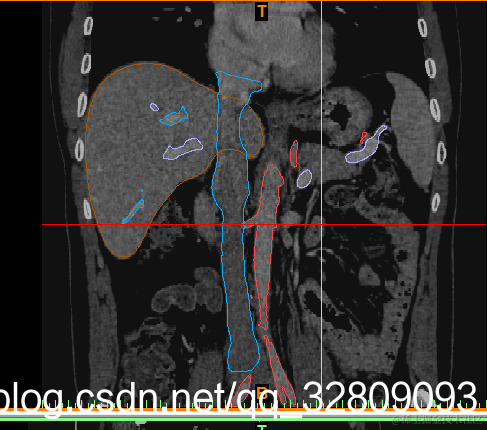

最后建模出来的效果:

正面图(肝脏+动脉+门静脉+腔静脉)                                反面图                                                          透视图

三种视图: